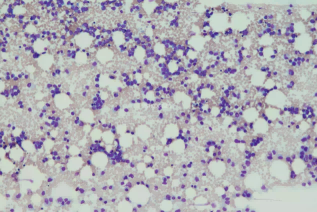

秦尤文、付兆強 | 上海市閘新中西醫(yī)結(jié)合醫(yī)院轉(zhuǎn)載自:檢驗醫(yī)學【前 言】非特異性酯酶(NSE)有多種,根據(jù)反應所需的pH不同分為酸性,堿性及中性NSE,包括α-醋酸萘酚酯酶(α-NAE),醋酸AS-D萘酚酯酶(NAS-DAE)等。其染色結(jié)果及特點可以作為急性白血病的輔助診斷,在鑒別急性粒細胞白血病和急性單核細胞白血病時尤其有用。通常認為原始粒細胞α-NAE染色呈陰性…